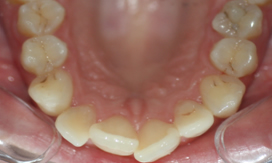

Figura 3. Fotografía un mes después de la intervención del higienista bucodental mostrando técnicas de higiene concretas y motivando al paciente con metas a corto plazo.

- Toma de registros fotográficos intraorales (Fig. 5)para valorar el estado de lesiones cariosas detenidas, y su evolución a lo largo del tiempo.

Figura 5. Fotografía intraoral que comparar a lo largo de las visitas del paciente para poder comprender la relación entre una higiene adecuada y la no progresión de la patología cariosa.

En estas revisiones se realizarán controles de placa, sondajes y las mediciones establecidas en el paso 1 para que el paciente pueda valorar apropiadamente la evolución en el tiempo, si es necesario mejorar la higiene en algún punto, o si tiene alguna duda, siendo de especial utilidad el control por imágenes (Figuras 2 y 3).